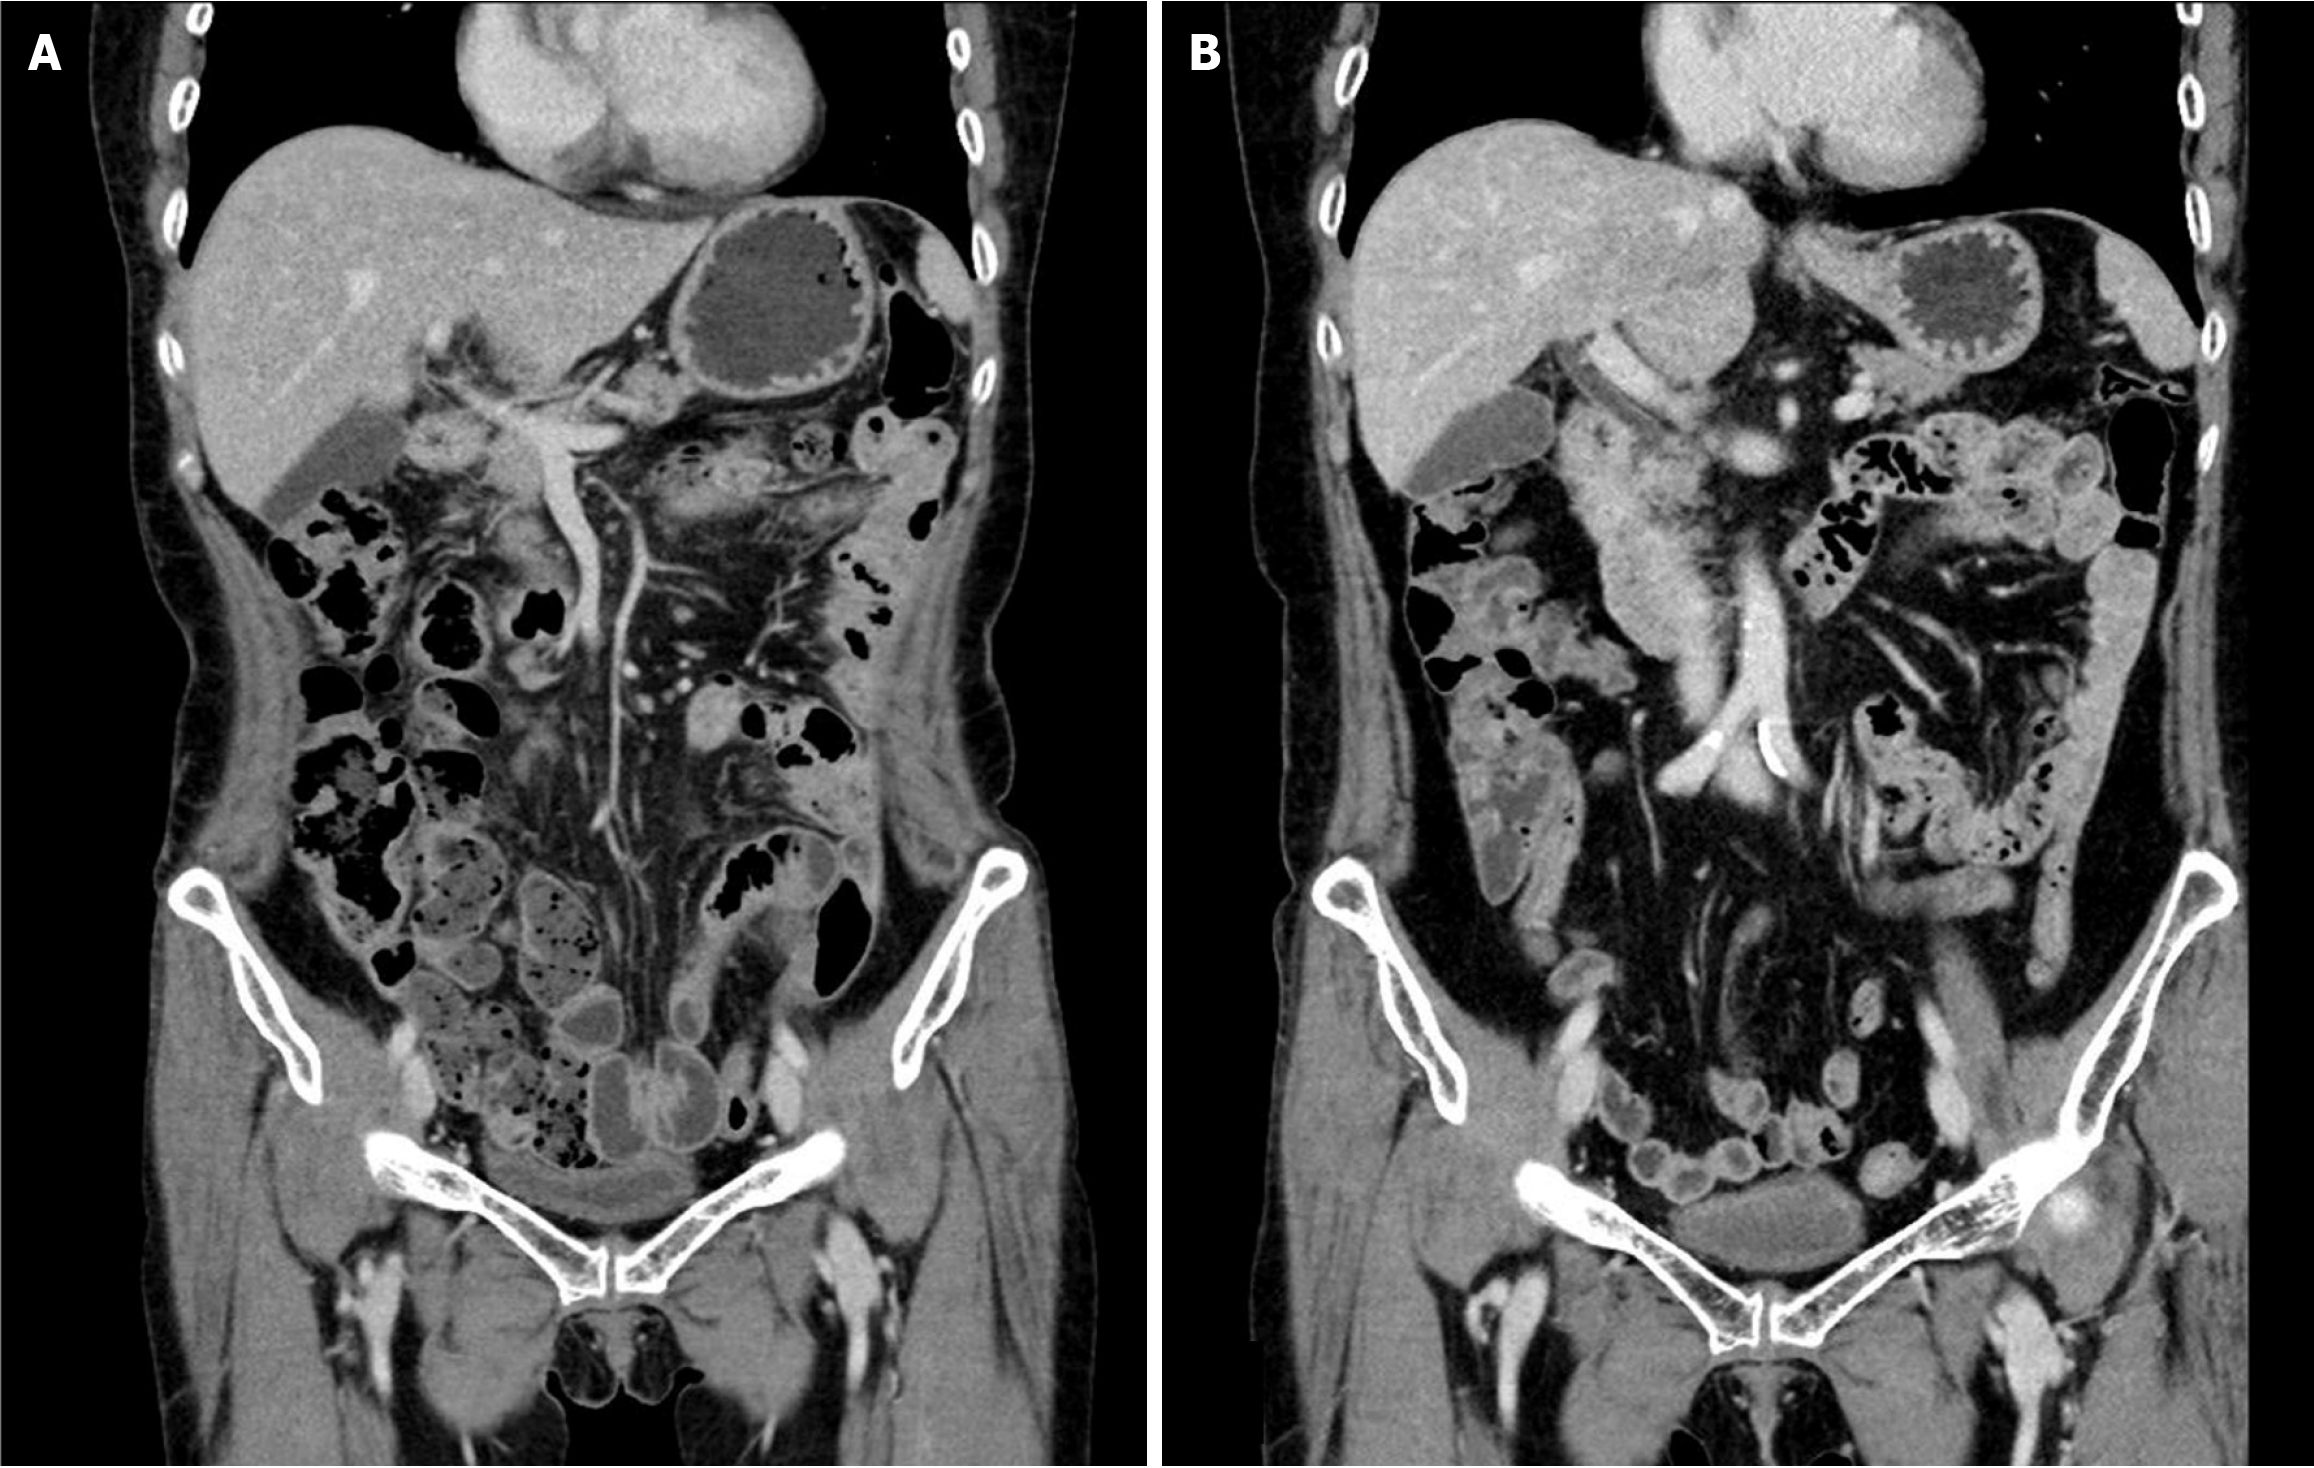

Intraperitoneal chemotherapy with 5-fluorouracil was administered on postoperative days 37 to 40. Palliative chemotherapy (FOLFIRI + bevacizumab) was scheduled for postoperative days 68 and 81 but was not administered due to thrombocytopenia and neutropenia, respectively. On postoperative day 103, in consideration of the patient’s overall state, the chemotherapy regimen was altered to oral capecitabine (1300 mg, twice a day). The treatment was conducted in a cycle of 2 weeks of medication followed by 1 week of cessation. AP-CT and tumor marker tests were conducted at three-cycle intervals to evaluate the patient’s response to chemotherapy. Before the 5th chemotherapy cycle, neutropenia occurred, necessitating dose reduction; in addition, hand-foot syndrome developed during the 14th cycle. In the 16th chemotherapy cycle, a second dose reduction was implemented due to a decline in the patient’s condition and exacerbation of hand-foot syndrome. Following the completion of 19 cycles of chemotherapy, the patient’s overall condition deteriorated, and her hand-foot syndrome worsened. Chemotherapy was discontinued after no signs of recurrence were observed upon evaluation, including via CT (Figure 4A).

Following the conclusion of chemotherapy, AP-CT, chest CT, and tumor marker tests were conducted every 6 months, whereas esophagogastroduodenoscopy and colonoscopy were performed annually for the first 2 years. Subsequently, all follow-up examinations were conducted at annual intervals. The complete removal of the primary tumor was confirmed via follow-up colonoscopy (Figure 2B). No sign of recurrence was observed up to 6 years post-surgery (Figure 4B), and routine follow-up is planned for up to 10 years.